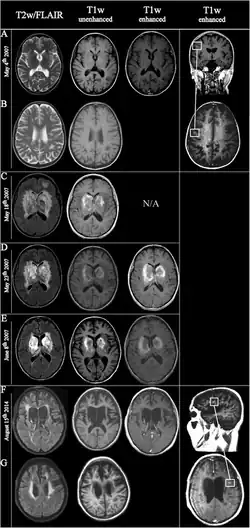

![]() | |

| Fulminating ADEM showing many lesions. The patient survived, but remained in a persistent vegetative state | |